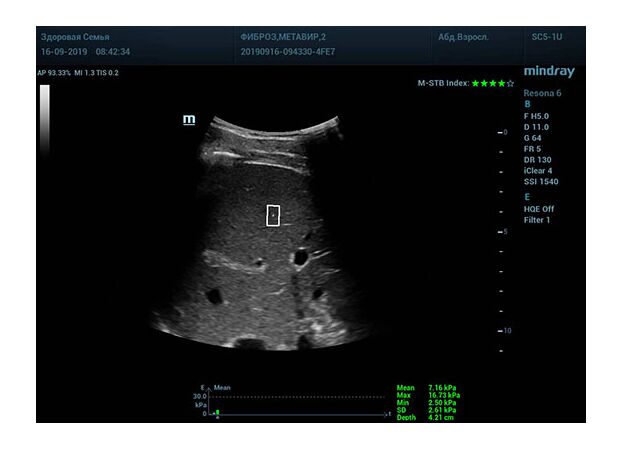

Определение плотности печени. Не ошибся ли оператор при измерении эластических свойств печени? Для оценки критериев качества предусмотрен индекс MBT, который покажет насколько «твердой» была рука оператора и двигалась ли печень. При MBT 5* рука тверда и показатели достоверны. Для оценки качества результатов используется IQR индекс, отображающий колебания показателей в точке измерения при расчете медианы. Показатели при IQR <30% считаются приемлемыми. Техника сканирования через межреберные промежутки требует размещение окна интереса на несколько сантиметром ниже капсулы, для исключения эффекта реверберации. Установка ROI на паренхиму без захвата сосудов, для исключения погрешностей измерения.

Стадия фиброза определяется по системе METAVIR Staging, построенной на данных биопсии и сопоставлении с данными эластографии. Своевременная диагностика фиброза, и начало его лечения, залог благоприятного исхода заболевания.